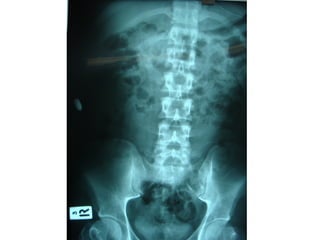

ชายไทย อายุ 38 ปี

อาชีพช่างรับเหมาก่อสร้า

ถูกยิง 3 นัดที่ท้องและขาซ

ก่อนมา รพ.ครึ่งชั่วโมง